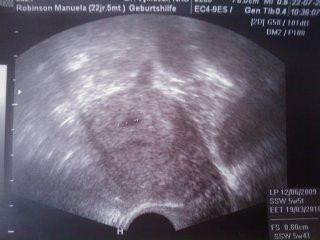

meine FH war auch total klein bei 5+5 zwei wochen spaeter war sie schon viel groesser also keine sorge.. es koennte sein das sich dein ES verschoben hat und das deshalb noch alles etwas klein ist.. hier is mal ein us bild bei 5+5 man kann kaum was erkennen

Hallo ihr lieben, vielen Dank für eure lieben Worte und eure Erfahrungen. DIe FH war nur 3,2 mm groß, das hat mich echt unsicher gemacht. scheint ja aber doch noch alles drinn zu sein:-)